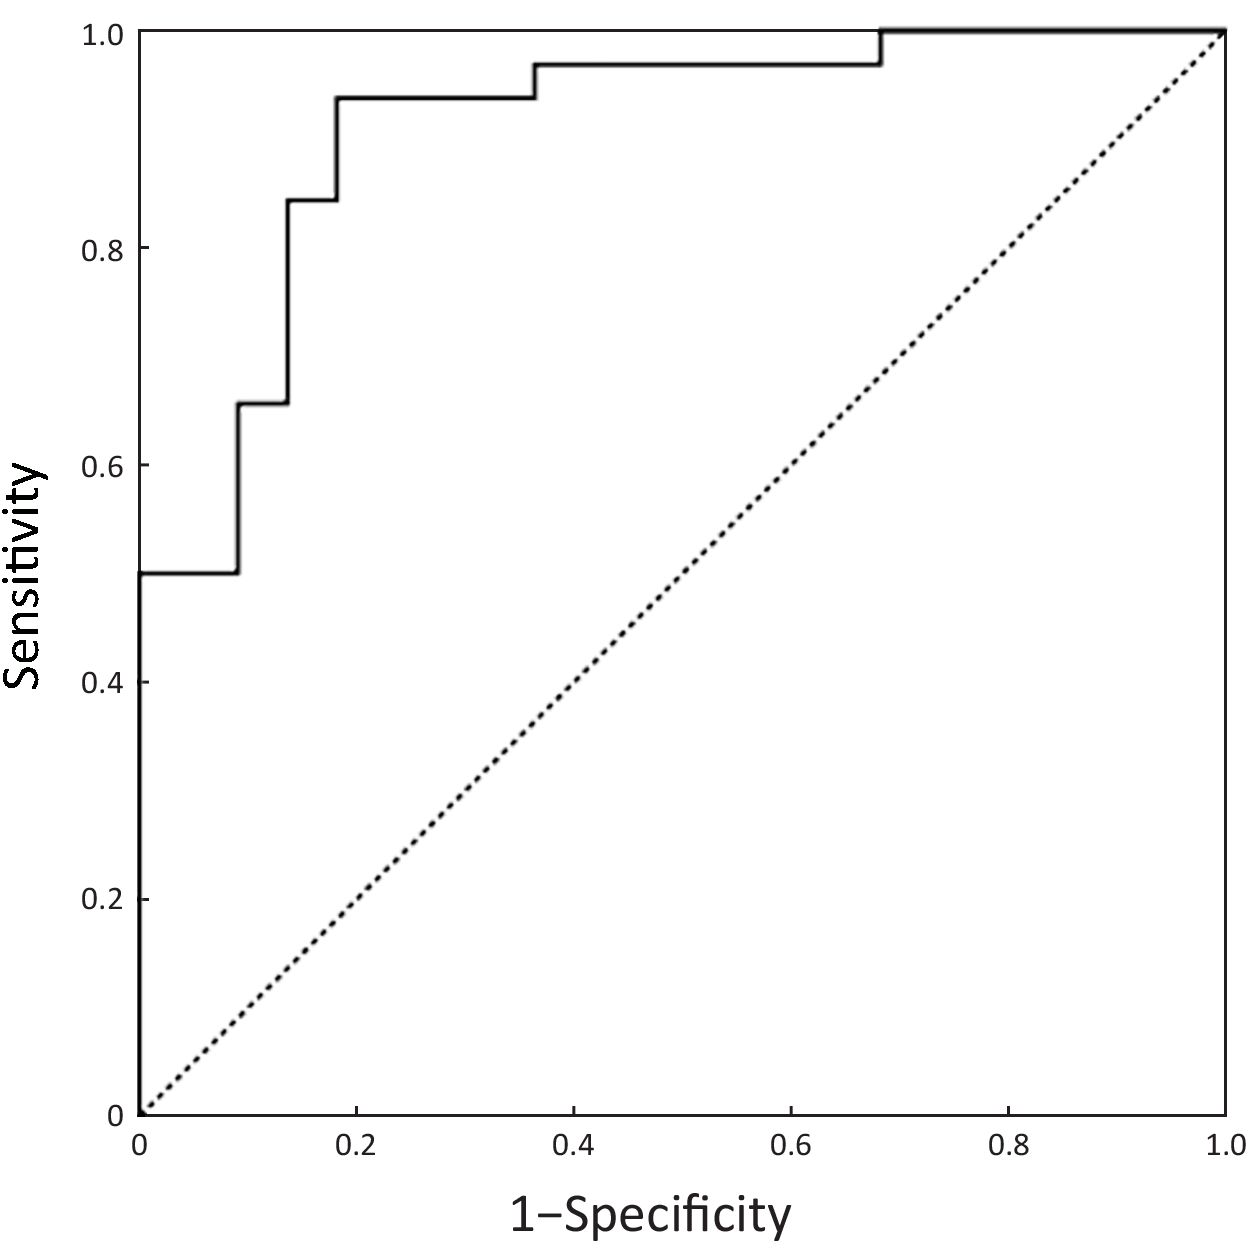

The imaging features which were significantly or nearly significantly different between the two groups (feeding arteries, intratumoral neovascularity, and enhancement area in the hepatic arterial phase, lymphadenopathy, T-A/AP, T-L/AP, and T-A/PVP) were included in binary logistic regression. Logistic regression showed that intratumoral neovascularity (P=0.015, OR=0.108, 95% CI, 0.018–0.646), lymphadenopathy (P=0.001, OR=0.055, 95% CI, 0.009–0.323) and T-A/PVP (P=0.004, OR=5.3E–5, 95% CI, 0.000–0.044) were independent factors for differentiation. When bootstrapping was performed to check the model validity, intratumoral neovascularity, lymphadenopathy and T-A/PVP were still statistically significant factors for differentiation (P=0.007, 0.003 and 0.007, respectively). These three CT features were used to construct the predictive equation as follows: Y = 13.937 – 2.228 × Intratumoral neovascularity – 2.908 × Lymphadenopathy – 9.846 × T-A/PVP.

Diagnostic performance of CT for differentiation

ROC curves of the predictive equation for differential diagnosis are shown in Figure 4. The AUC was 0.911 (95% CI, 0.831–0.990, P<0.001). The larger Y value represented the higher probability of poorly-differentiated GEP-NENs. A cut-off point of –0.21 was determined and patients with Y>–0.21 were judged to have CT-predicted poorly-differentiated GEP-NENs. The sensitivity, specificity, positive predictive value, negative predictive value and accuracy for predicting poorly-differentiated GEP-NENs were 93.8% (30/32), 81.8% (18/22), 88.2% (30/34), 90.0% (18/20) and 88.9% (48/54), respectively.

The distinction between LMs of poorly-differentiated NENs and LMs of well-differentiated NENs is one of the most important diagnostic steps with regard to significant differences in biologic behavior and therapeutic strategy between the two tumor categories. Our results showed that a lower T-A/PVP and the presence of intratumoral neovascularity and lymphadenopathy were more common in LMs of poorly-differentiated GEP-NENs (all P<0.05) and were also statistically significant factors for differentiating the two groups of tumors. Using the predictive equation which was constructed using the three independent discriminators, the diagnostic performance of CT for differentiating the two groups of tumors was 0.911 (AUC). This result indicated that CT was also useful in differentiating LMs with different pathologic grades, and may be helpful in selecting the most appropriate management strategy.